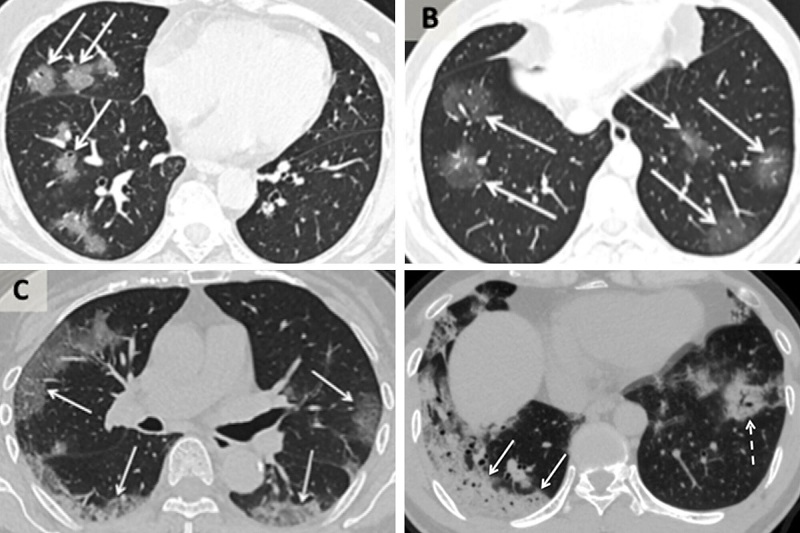

Коли вірус досягає легенів, їх слизові оболонки запалюються. Це може пошкодити альвеоли або мішечки легенів, і їм доводиться працювати старанніше, виконуючи свою функцію постачання киснем кров, яка циркулює по всьому тілу, і видалення вуглекислого газу з крові, щоб він міг видихатися.

Набряк і порушення потоку кисню можуть призвести до того, що ці області в легенях заповняться рідиною, гноєм і мертвими клітинами. Може виникнути пневмонія, інфекція в легенях.

Далі, за словами доктора Шу-Юань Сяо, вірус починається в периферичних областях з обох сторін легенів і рухається до верхніх дихальних шляхів і трахеї.

На комп'ютерній томографії в легенях зараженої людини видно туманну завісу, яку легко сплутати з іншими респіраторними захворюваннями.